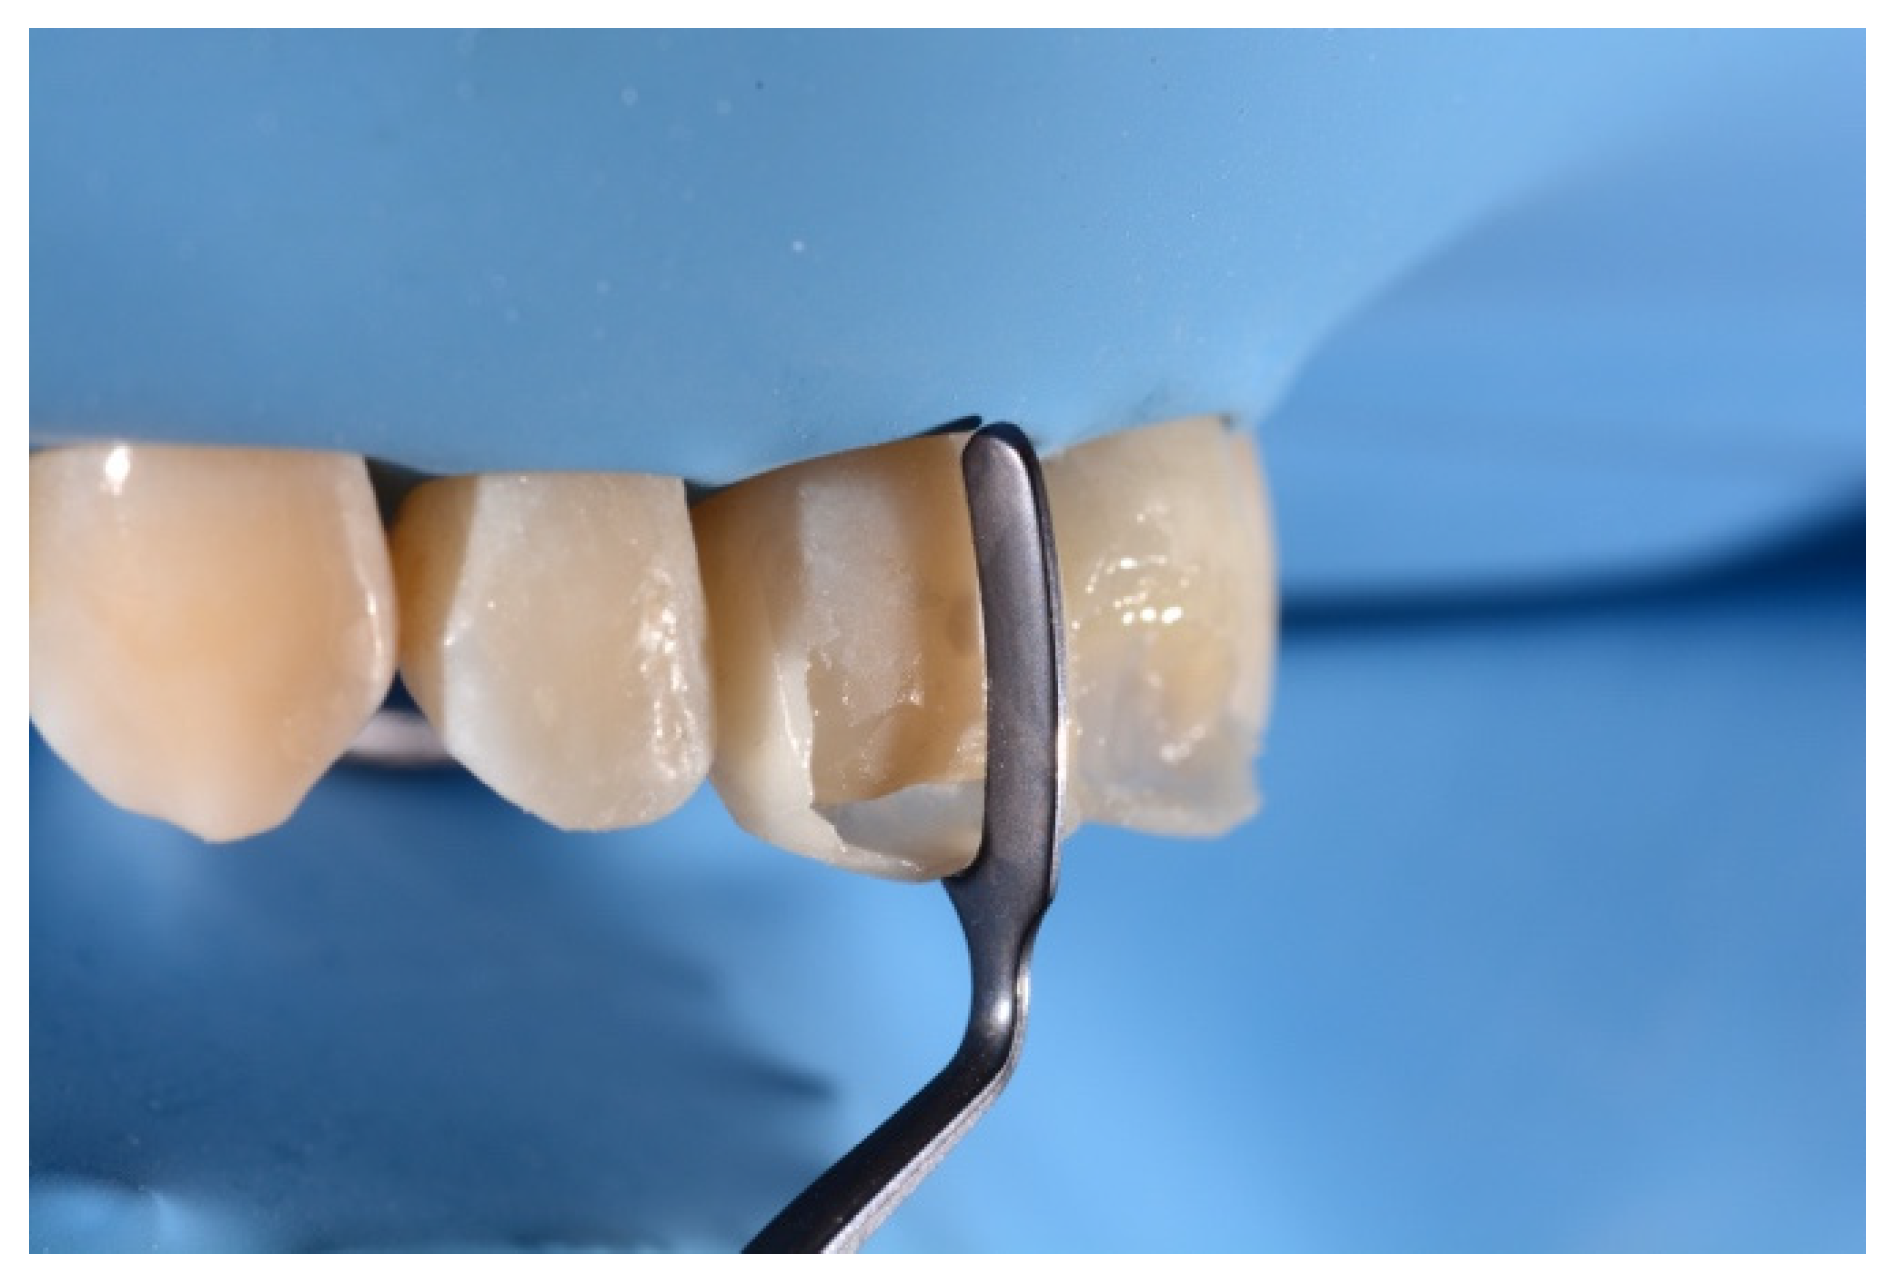

- Building interproximal walls with matrices;